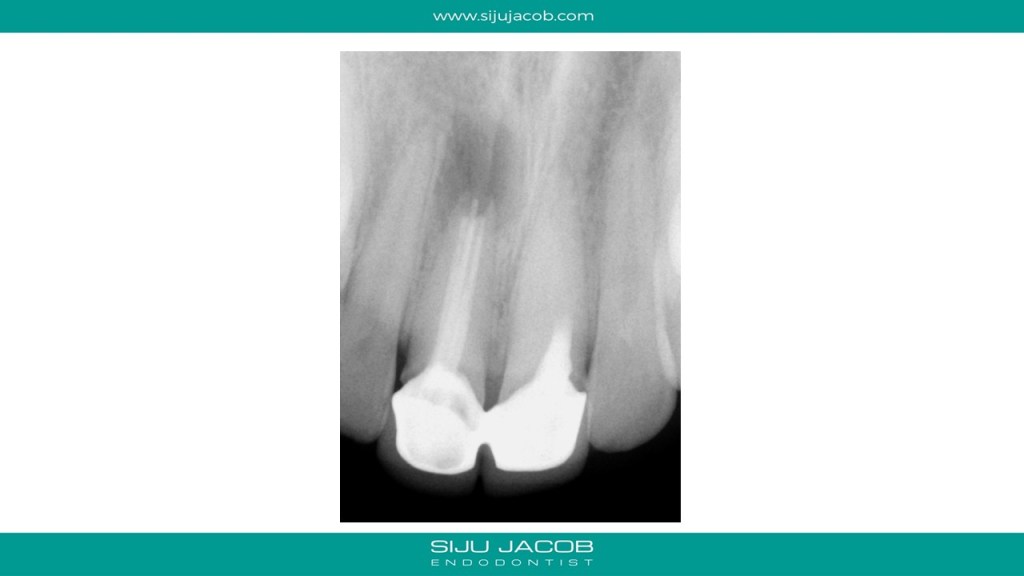

This was a patient who traveled from abroad from Treatment. We had only 9 days to do his treatment. So, we did endo and immediate surgery.